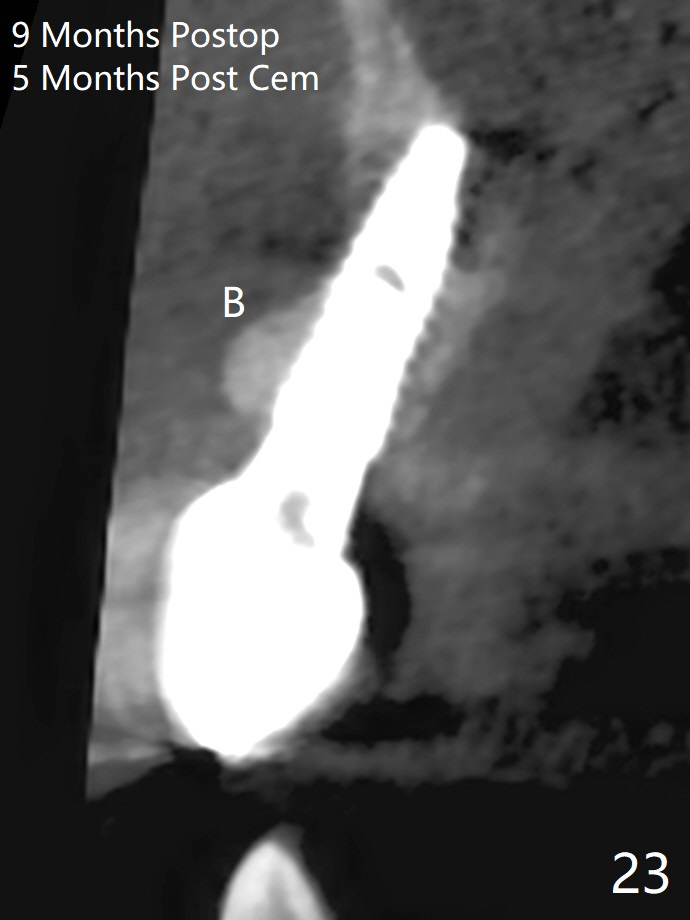

18岁男从外州大学回来,无症状,但是6号牙(右上尖牙)颊侧瘘道(图一,二(角化龈充分(箭头))),根尖片显示植体近中骨吸收(图三:*),而对侧植体仿佛骨整合(图四)。患侧切开后发现植体颊侧暴露,松动。拔除后骨缺损由粘性骨粉修复(图七,九:*),覆盖PRF膜(图七:P)和带钛网(图九:^)不可吸收膜(图五-七),后者用两个小钉子固定(图六(腭侧),七(颊侧),九),使用新的刀片和一个特殊尖头剥离器在颊侧骨膜下相当广泛分离,使用PTFE缝线,粘膜下水平褥式缝合之后(图八:箭头),多个垂直间断缝合,两个乳头垂直褥式缝合。术后一周伤口没有裂开,术后疼痛肿胀已经消退(图十)。术后十八天牙槽嵴仿佛比对侧还要宽(图十一,三与图十二,四(取模)对比)。术后5.5个月伤口没有裂开,牙槽骨,角化龈宽(图十六),与钛网和两个小钉子固定有关(图十五,十七)。CT显示牙槽骨只能容纳2.5或者3.0毫米植体(图十八)。11号牙植体牙冠粘固后没有骨质吸收(图十九),其实10,11号牙颊侧骨板隆起(图二十至二十二),而6植体失败,颊侧骨板吸收,甚至累及5号牙(图十七)。